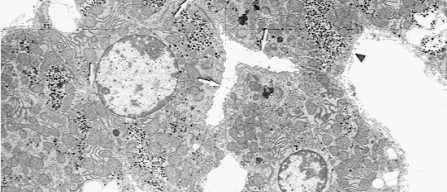

Nesta práctica imos extraer DNA dun tecido, no noso caso fígado. Este tecido é moi axeitado xa que conten relativamente pouca substancia intercelular e os hepatocitos teñen un núcleo bastante grande en relación co citoplasma.